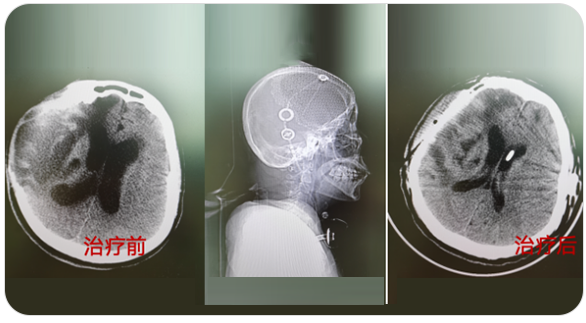

精通颅内动脉瘤介入栓塞和手术夹闭双技术,系统掌握脑动静脉畸形、颈内动脉海绵窦漏、硬脑膜动静脉漏等颅内血管疾病的诊疗和手术,精通颈动脉、椎动脉狭窄的血管内重建技术,以及颈动脉狭窄的内膜剥脱手术技术。在颅内肿瘤、椎管内肿瘤、颅脑损伤、高血压脑出血等疾病的诊治和手术,脑功能性疾病立体定向手术治疗等方面也积累了丰富的经验。

从事神经外科工作30年,擅长脑与脊髓血管类疾病、肿瘤、外伤等疾病的诊断与治疗,尤其擅长神经介入治疗各类脑血管疾病。累计完成介入栓塞颅内动脉瘤2000多例,颅内血管畸形数百例,夹闭颅内动脉瘤数百例,手术颅内与脊髓肿瘤数百例。在脑和脊髓血管病、肿瘤、外伤等方面有丰富的经验和较深造诣。